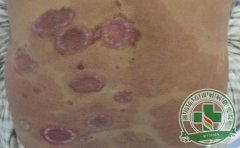

银屑病俗称牛皮癣,是一种常见的皮肤病,生活中诱发的原因有很多,对患者造成的伤害也是很大的,不少患者在疾病出现后,不知道如何有效的控制,导致病情延误,产生严重的伤害 [详细]

银屑病是一种顽固性的皮肤病,俗称牛皮癣,目前是医学界上的一大难题,银屑病一般在发病的时候,皮肤上会伴有不同程度的瘙痒,给患者的身心健康都造成严重的伤害。那得了银 [详细]